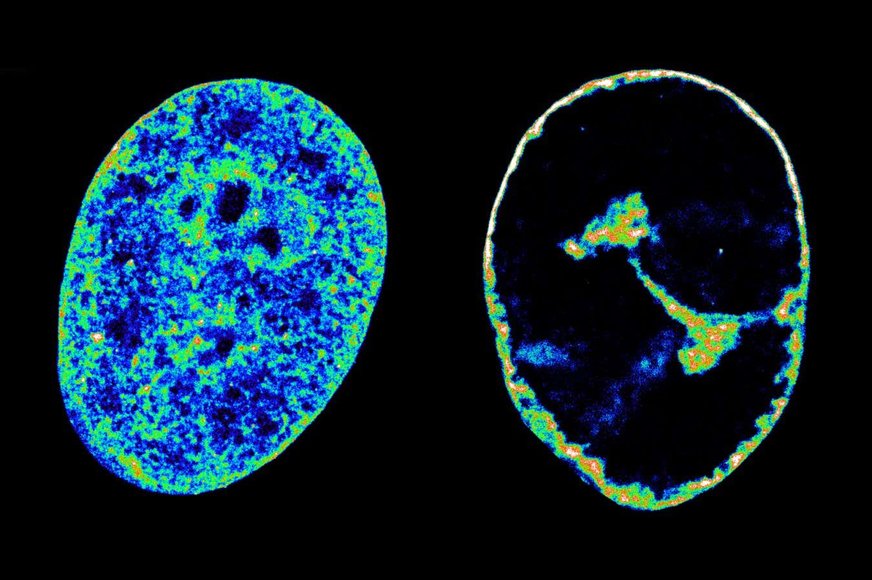

Kľúčové je, že štúdia preukázala, že blokovanie špecifického hostiteľského enzýmu, topoizomerázy I, úplne zastavilo schopnosť HSV-1 reorganizovať genóm, čím sa infekcia účinne zastavila predtým, ako vírus dokázal vyprodukovať jedinú novú časticu. Toto "nepriateľské prevzatie" vedie k kolapsu transkripcie v celom hostiteľskom genóme, čo spôsobí, že chromatín – prirodzený stav ľudskej DNA – sa stlačí do hustej škrupiny, ktorá zaberá len 30 % svojho pôvodného objemu.

Výskumníci použili pokročilé techniky, ako je superrozlišovacia mikroskopia, schopná vizualizovať štruktúry s veľkosťou len 20 nanometrov (20 x 10^-9 metrov), a Hi-C, ktorá mapuje interakcie DNA, aby odhalili tieto zložité procesy.   Objav, že inhibícia jediného hostiteľského enzýmu môže úplne zabrániť vírusovému prevzatiu, je mimoriadne významný.

Zdroj Foto: CRG / Esther Gonzalez Almela and Álvaro Castells García